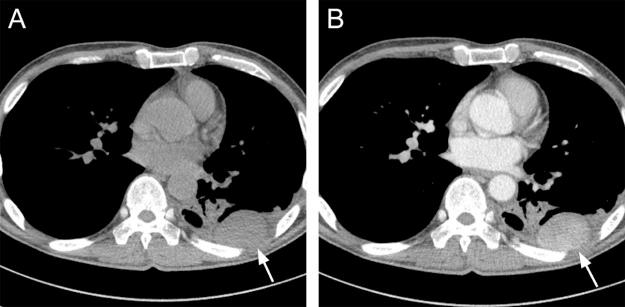

Castleman's disease presenting as a pleural tumor: a case report with CT findings.

Castleman's disease (CD) is an uncommon benign lymphoproliferative disorder which most commonly involves the mediastinum but rarely affects the pleura. We report a case of unicentric CD that presents as a pleural mass in a 45-year-old man, which was subsequently resected followed by an unexpected diagnosis on histologic examination. Although rare, CD should be included in the differential diagnosis of well-enhancing pleural mass.